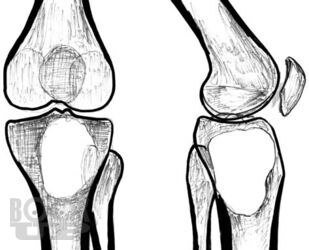

Рентгенологические и ультразвуковые исследования при заболеваниях суставов

Семизоров А. Н. Рентгенологические и ультразвуковые исследования при заболеваниях суставов : Пособие для врачей / А. Н. Семизоров, С. В. Романов. - М. : Видар-М, 2008. - 216 c. - ISBN 9785884291140. - Текст : электронный // ЭБС "Букап" : [сайт]. - URL : https://www.books-up.ru/ru/book/rentgenologicheskie-i-ultrazvukovye-issledovaniya-pri-zabolevaniyah-sustavov-9194384/ (дата обращения: 23.05.2026). - Режим доступа : по подписке.

Предлагаемая книга является дальнейшим развитием вышедшего ранее пособия «Ретнгенологическое и ультразвуковое исследование при заболеваниях

суставов».

Иллюстративная часть материала дополнена рентгенограммами, расширен

и углублен текст. В книге изложены основы рентгенологической и ультразвуко

вой диагностики дегенеративнодистрофических, воспалительных и других

заболеваний суставов. Представлены особенности диагностики при наиболее

часто встречающихся в клинической практике заболеваниях суставов.

Пособие рассчитано на рентгенологов, врачей УЗИ, ортопедов и врачей других специальностей.